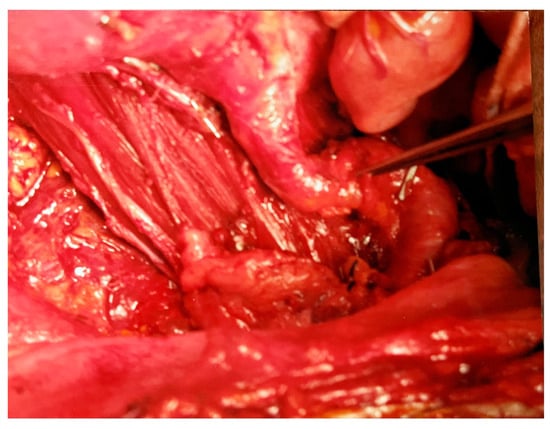

Figure 3. Marked right iliac artery deviation and psoas muscle after tumor resection.

2.7. Actual Outcome

During the surgery, a huge tumor mass involving and deviating towards the right retroperitoneal structures including the colon, duodenum, and vascular structures—anterior and to the left—was found. During surgery, we were able to encircle and remove a major en bloc portion of the tumor (greater than 13.5″ or 35+ cm in cross section and greater than 38″ or 98 cm in diameter) along with a portion of the right colon (Figure 1, Figure 2 and Figure 3). Her weight, after surgical resection, dropped from 125 pounds to 79 pounds. The excised tumor mass overflowed and covered the entire surgical scrub basin margins. Following an uncomplicated recovery, she regained her weight and returned to work as a supervisor.

During the multiple surgical procedures, this patient had approximately 120 pounds of liposarcoma removed. The photographs demonstrate the enormity of one of the tumor resections and the surgical difficulty encountered during the resection. We were able to monitor the tumor progress palpably and with recurrent X-rays, computerized tomography scanning, and ultrasounds, and to periodically palliate the disease process surgically, but we were not able to cure the tumor. None of the referenced articles discussed a loss of renal function due to tumor encroachment as being related to the demise of the patient.

4. Conclusions

This patient was aware of her diagnosis (a huge recurrent liposarcoma of the retroperitoneum) and prognosis when initially seen by us for palliative care. But, after some discussion, despite her diagnosis, we were able to provide options and a treatment program enabling her to return to productive employment for more than a decade. She elected to follow a palliative course, which provided her with many years of fruitful employment as well as the enjoyment of her family and friends. Despite her diagnosis and the rigors of treatment, as exemplified by the photographs, she had very positive surgical palliative results until the potential need for chronic dialysis after the completion of a nephrectomy and pancreatectomy.